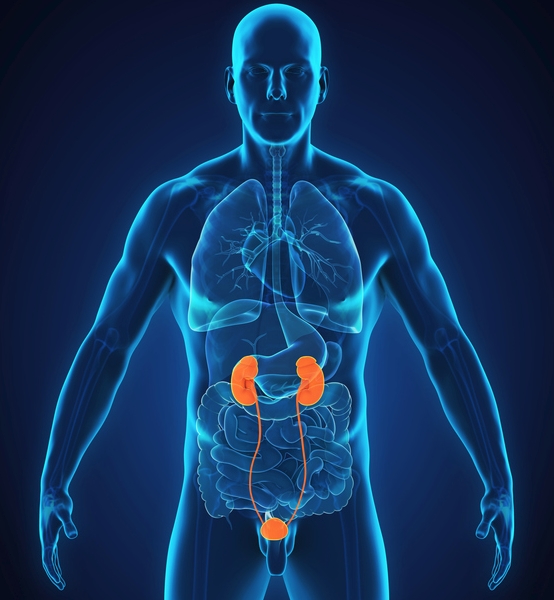

신부전증과 투석

신장의 기능이 85~90% 이상 상실되면, 투석이라는 치료를 고려하게 됩니다.

- 혈액투석: 정맥에 관을 꽂고 기계로 노폐물을 제거

- 복막투석: 배 안에 투석액을 주입해 체내에서 정화

일주일에 2~3번 병원에 다니는 게 쉽진 않지만, 삶을 유지할 수 있는 소중한 방법이에요.

신부전증 단계별 특징

신부전증이란 1단계부터 5단계까지 나뉘어요. 이걸 ‘GFR 수치(사구체 여과율)’로 판단하는데, 수치가 낮을수록 심각한 상태랍니다.

| 단계 | GFR 수치 | 상태 | 주요 특징 |

|---|---|---|---|

| 1단계 | 90 이상 | 정상에 가까움 | 증상 거의 없음 |

| 2단계 | 60~89 | 경증 손상 | 단백뇨 가능성, 피로감 |

| 3단계 | 30~59 | 중등도 손상 | 붓기, 소변 변화 |

| 4단계 | 15~29 | 중증 손상 | 식욕 저하, 고혈압 |

| 5단계 | 15 이하 | 말기신부전 | 투석 또는 이식 필요 |

이 수치만 알아도 내 콩팥 건강을 대략 짐작할 수 있어요.